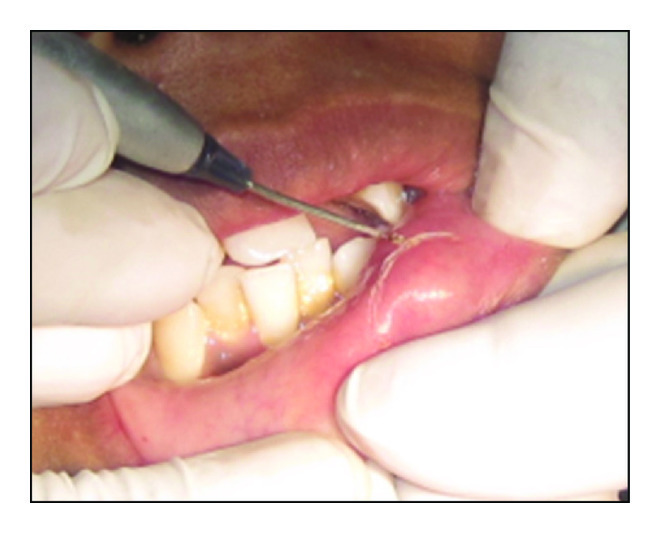

A 16-year-old female presented with a swelling in the lower left labial mucosal region for the past few months. She complained of intermittent swelling which often bursts and disappears for a few days. On clinical examination, lesion was soft, painless, fluid-filled, and approximately 1 × 1 cm in size (Figure 1). The history and clinical presentations were consistent with mucocele. Various treatment modalities such as surgical incision, cauterization, and laser excision were explained to the patient’s guardian and obtained willingness to perform the most recent treatment option of laser excision.

Following minimal infiltration of 1 : 2,00,000 Xylocaine, the lesion was excised using soft diode laser in wavelength of 940 nm, 400 μm diameter tip at 1.5 W in continuous mode. The incision was placed on the uppermost site of the lesion and complete excision was performed (Figures 2, 3(a), and 3(b)). The specimen (Figure 4) was subjected to histopathological examination and showed cystic cavity lined by thick fibrous capsule. Cystic lumen contains mucin, foamy macrophages, and chronic inflammatory cells. Areas of coagulation necrosis surrounding the intended biopsy material were also evident. Adjacent mucous salivary gland was also seen. With all these histopathological features, diagnosis of mucous extravasation cyst was given (Figures 5 and 6). Patient was prescribed analgesics. There was uneventful healing on 45 days of follow-up (Figures 7, 8, 9, 10, and 11).